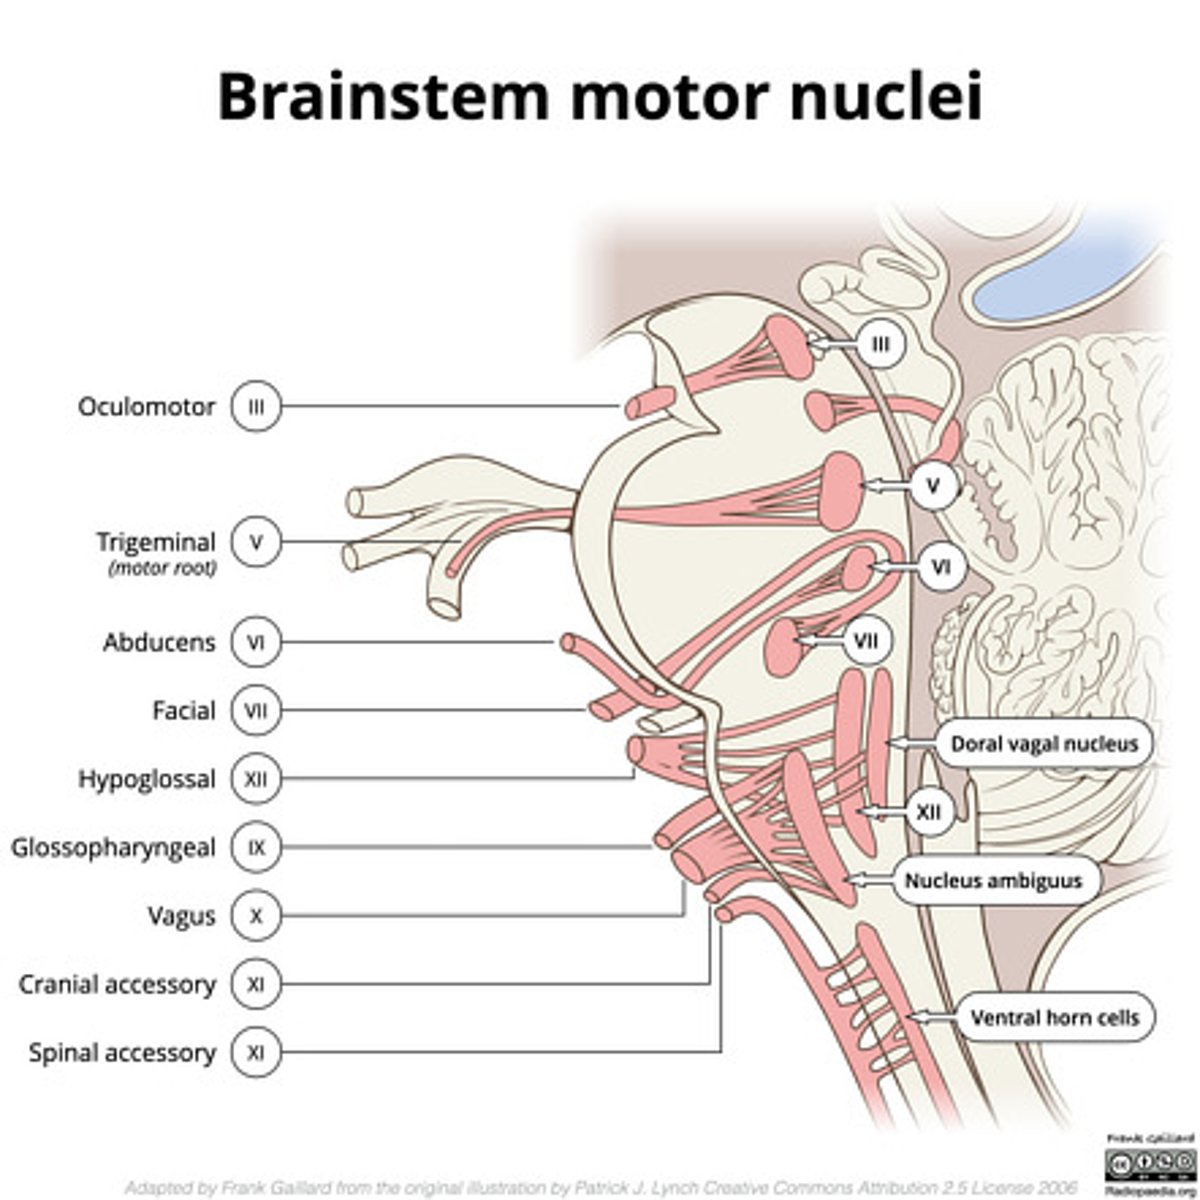

What cranial nerve nuclei are in the tegmentum pons?

1. CN V (5)

2. CN VI (6)

3. CN VII (7)

4. CN VIII (8)

What nuclei are at the pontomedullary junction?

1. SVE of CN VI

2. SVE of CN VII (facial)

What are the facial colliculi?

bumps (hills) coming out from dorsal pontomedullary junction into the 4th ventricle -- CN VII SVE fibers create this space when they wrap around the abducens nucleus

Where do CN VI, VII, VIII exit the pons?

pontomedullary junction

What is the spacing of CN VI, VII, and VIII exiting the pontomedullary junction?

8 & 7 -- lateral and closer together

6 -- medial and far away

image -- look at red font